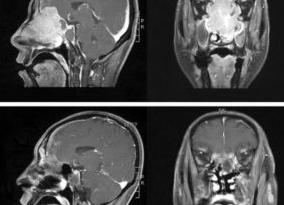

МРТ пазух носа с визуализированным новообразованием — возможность рассмотреть наличие патологических образований

Также метод даёт полную картину решетчатых и клиновидных пазух. Это важно, так как полости находятся «неудобно», глубоко в черепе, что затрудняет диагностику другими методами. С помощью МРТ придаточных пазух носа можно увидеть незначительные дефекты слизистых, что в дальнейшем может подтолкнуть на развитие заболевания.

Часто определяют утолщение стенок носовых пазух и воспалительный процесс в них, и, конечно же, с помощью метода можно определить развитие опухолей.

Что показывает МРТ? С помощью магнитно-резонансной томографии можно с точностью определить доброкачественных, злокачественные или мягкотканные опухоли, так как именно этот способ предназначен для исследования мягких тканей. Помимо этого, новообразования можно замерить, определить точное расположение и отношение их к тканям, лежащих рядом.

Также определяется интенсивность кровотока, относящегося к опухоли. Патологии и заболевания в костных областях пазух носа с помощью МРТ выявляются не самым точным образом. При подозрениях к костным патологиям носа, лучше проводить компьютерную томографию.